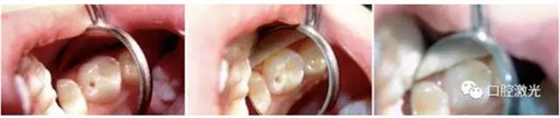

案例1:兒童口腔去齲

9歲男童上左側磨牙溝窩齲齒。整個治療過程無需麻醉。

案例2:成人口腔去齲

39歲男性患者,下右側牙頸部齲。治療過程無需麻醉